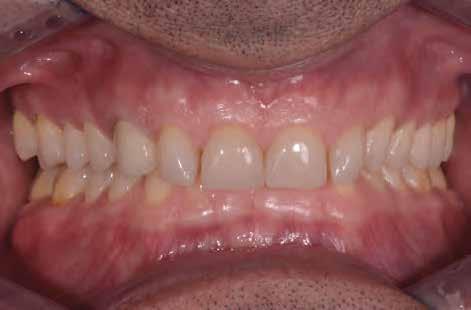

A cikkben egy fiatal nő kezelésének interdiszciplináris megközelítését foglaltuk össze, aki fogászati állapota miatt hoszszú ideje szenvedett fizikálisan és pszichésen is (1. ábra)

1. a–c ábrák: Kiindulási helyzet: fiatal páciens komoly fizikai és pszichés szenvedéssel.